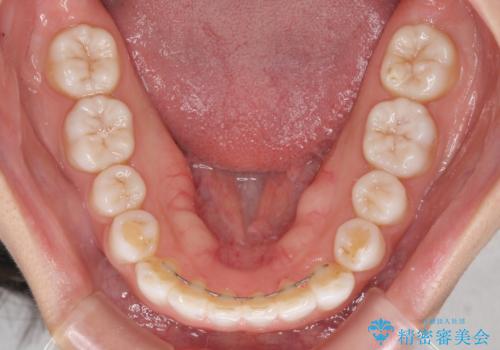

どこまで口元を引っ込めることができるのか、患者様自身も正直分からない部分があったため、少しずつ治療ゴールを変更しながら仕上げていきました。

気になっていた前歯の飛び出した印象は、最終的にはスッキリと引っ込み、大変満足していただきました。